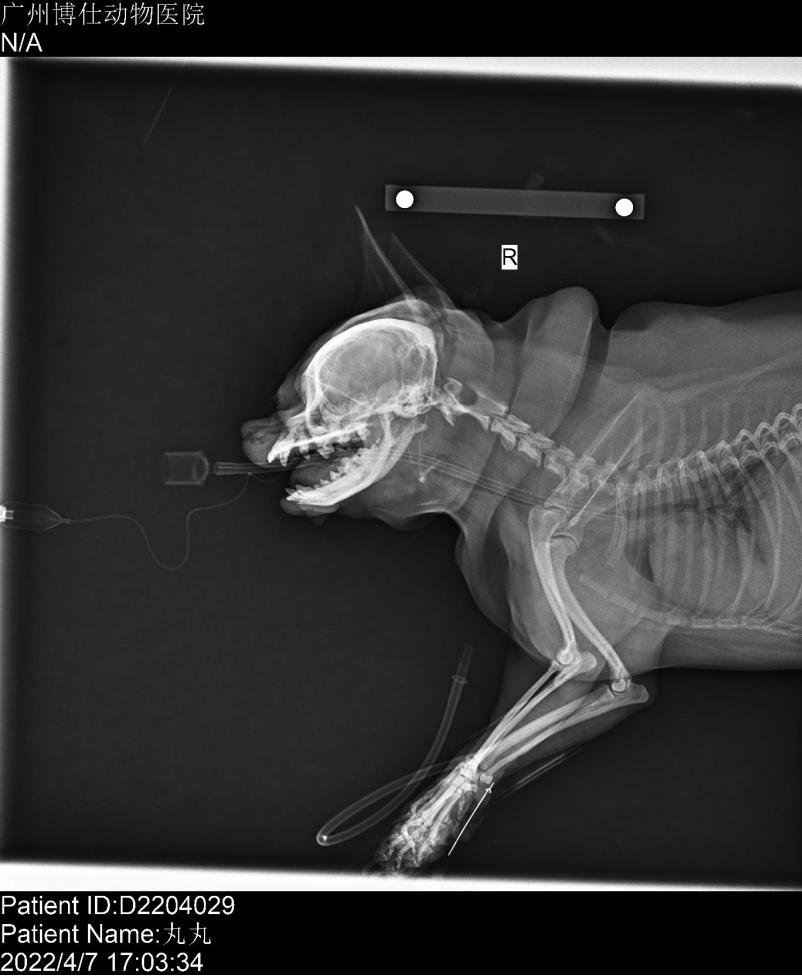

●喉部X光拍摄,需要对该狗进行镇静拍片,使用的镇静药为丙泊酚,8mg/kg。打上留置针,镇静前3分钟进行预吸氧,准备好4.5号4号3.5号插管。

缓慢通过留置针向静脉推注丙泊酚,该犬1分钟后出现舌头颜色变紫,喉部声响,插上气管插管后吸氧并给予正压通气支持,20s后该犬舌头颜色恢复正常呈粉红色,观察喉部发现软腭过长会盖住会厌软骨,整个喉部红肿,喉囊囊肿。

该犬呼吸稳定进行喉部X光片拍摄,可见喉部骨骼结果正常,气管未见异常,肥胖导致皮肤褶皱。